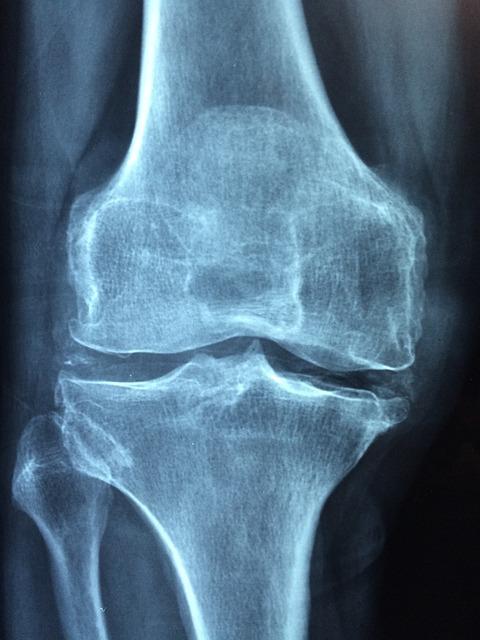

Artróza kolene je degenerativní onemocnění kloubů, které postihuje miliony lidí po celém světě. Tento stav se vyznačuje opotřebením chrupavky, což vede k bolesti, ztuhlosti a omezené pohyblivosti. Příčiny artrózy kolene mohou být různé, zahrnující:

Odpověď: Artróza kolene je degenerativní onemocnění kloubů, které se vyznačuje postupným opotřebením chrupavky. Hlavními příznaky jsou bolest v koleni, ztuhlost, otoky a omezená pohyblivost. Často se také projevuje pocitem křupání při pohybu.